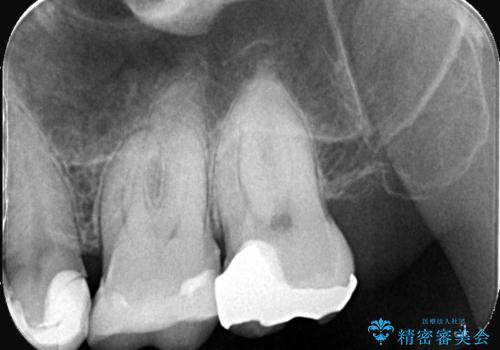

- 患者様は、左上7のメタルインレー(銀の詰め物)の見た目が気になるとのことで来院されました。診察したところ、メタルインレーの下にむし歯の再発リスクがあることも確認。より審美性と耐久性を高めるため、メタルインレーを除去し、セラミッククラウンで補綴する治療計画を立てました。

メタルインレーを丁寧に除去し、歯の状態を確認。その後、精密な形成を行い、適合性の高いセラミッククラウンを装着しました。セラミッククラウンは天然歯に近い見た目で、美しさだけでなく強度や機能性にも優れているため、患者様にも「自然な仕上がりで違和感なく噛める」と大変ご満足いただきました。